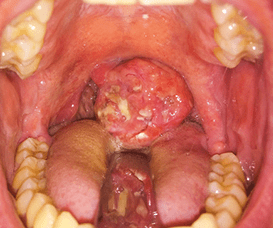

4. Enlarged Tonsils or Lingual Tonsils

6. Rare Causes (Cancer)

Usually with:

- Weight loss

- Pain

- Blood

- Progressive swallowing difficulty

- Mouth & neck exam

- Flexible nasoendoscopy

Globus sensation is often benign but never ignored. Direct throat visualisation is essential to exclude cancer and structural disease. Accurate diagnosis prevents unnecessary medication and anxiety.